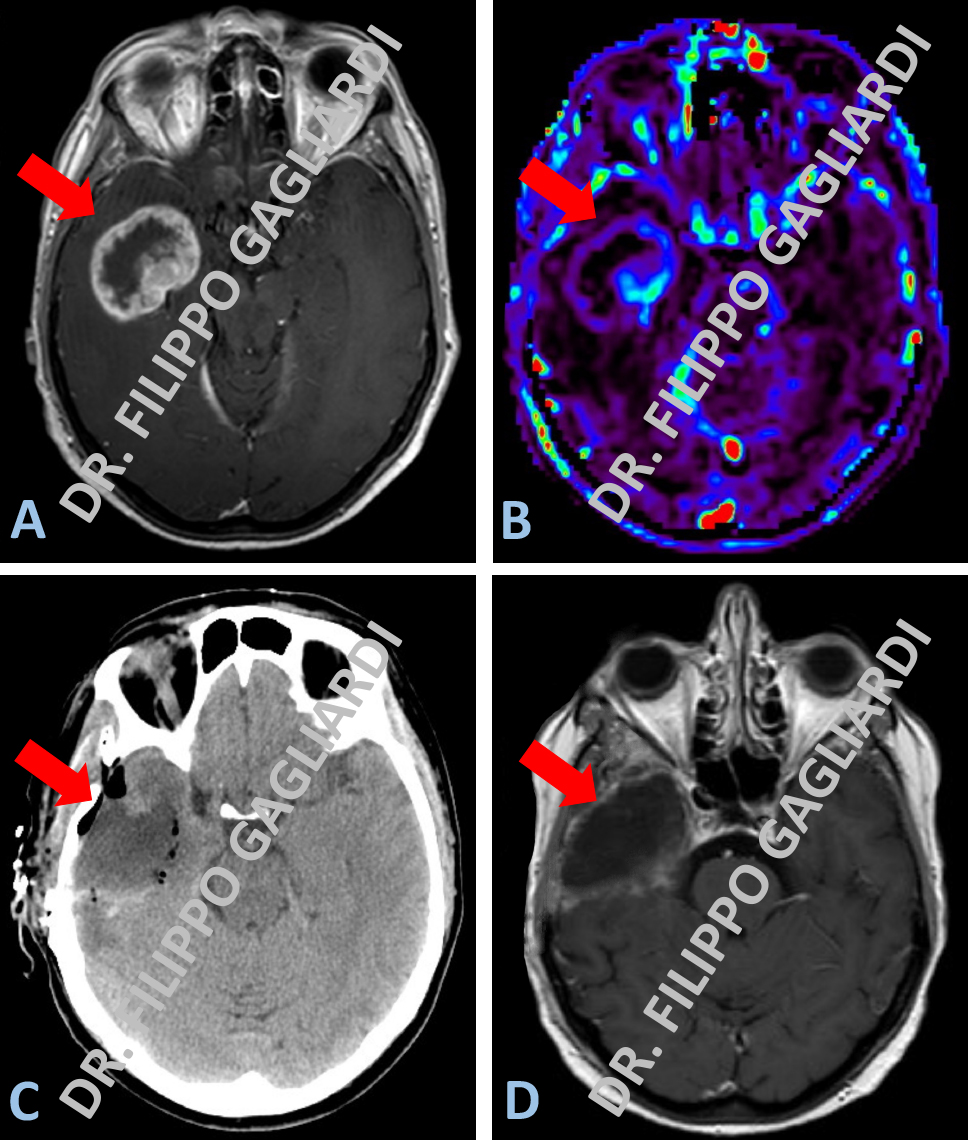

Caso di linfoma primitivo cerebrale in una Paziente sottoposta a biopsia stereotassica. La biopsia stereotassica è una procedura ad altissima precisione. Attraverso un sottile ago, consente di prelevare tessuto cerebrale per eseguire una diagnosi istologica nel caso di patologie intracraniche. Il sistema stereotassico si avvale di un casco che viene posizionato al paziente prima della procedura bioptica e che rappresenta un sistema di massima affidabilità per la localizzazione di target intracranici. Questa metodica minimizza i rischi di complicanze e massimizzare le possibilità diagnostiche in caso di lesioni profonde in aree critiche. La figura A mostra l’esame spettroscopico preoperatorio. Si tratta di un esame non invasivo. Viene eseguito con l'apparecchiatura di RM che, campionando il tessuto patologico, ne analizza la composizione chimica. L’esame era suggestivo, per l’elevata concentrazione di alcuni elementi chimici, per linfoma primitivo cerebrale. La figura B mostra lo studio di RM standard con mezzo di contrasto, che definisce la morfologia della lesione a livello del tronco dell’encefalo. Infine la figura C illustra invece il controllo della TC post-operatoria, dove si può apprezzare la precisione del prelievo bioptico (area nera).

Craniotomia ed exeresi di lesione gliale in caso di glioblastoma (tumore altamente maligno) temporale destro in un uomo adulto. La figura A mostra lo studio di RM pre-operatoria con il mezzo di contrasto. Nella figura B sono documente le sequenze con lo studio di perfusione. La lesione prende il contrasto “ad anello”, ovvero presenta la caratteristica area di necrosi centrale dovuta alla rapida crescita cellulare, mentre la parte più periferica risulta molto vascolarizzata (prende contrasto), a dimostrazione dell’elevata aggressività biologica della malattia. Il Paziente è stato sottoposto ad un intervento di craniotomia ed exeresi radicale della lesione gliale. La figura C mostra la TC post-operatoria dove si apprezza la cavità chirurgica rimasta dopo la asportazione totale della malattia. Alla RM, eseguita a 3 mesi dall’intervento (figura D), si conferma l’assenza di tessuto patologico con la preservazione dell’integrità del tessuto cerebrale sano.